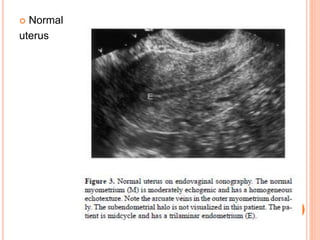

 Normal

uterus

ULTRASOUND  Sonographic featuresof adenomyosis are variable and may be absent.  The reported sensitivity and specificity of trans- abdominal ultrasound are 32-63% and 95-97% respectively 7.  The spectrum of findings includes:  Normal appearing uterus  Focal or diffuse myometrial bulkiness, typically of the posterior wall .  Thickening of the transition zone can sometimes be visualised as a hypoechoic halo surrounding the endometrial layer of ≥12 mm thickness

 Subendometrial echogeniclinear striations  Subendometrial echogenic nodules (specific sign)  Small myometrial cysts / sub endometrial cysts (specific sign)  Heterogeneous echogenicity (heterogenous myometrial echotexture)  hyperechoic: islands of endometrial glands  hypoechoic: associated muscle hypertrophy  a "Venetian blind" appearance may be seen due to subendometrial echogenic linear striations and acoustic shadowing where endometrial tissues cause a hyperplastic reaction